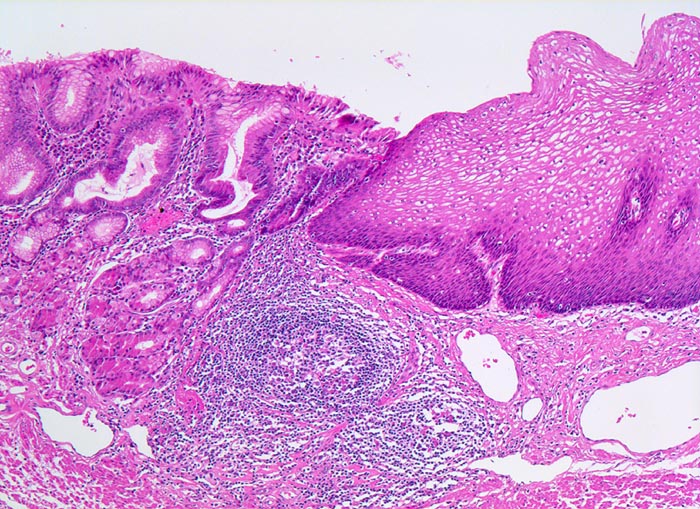

Makroskopisch finden sich zungenförmige, nach proximal reichende rötliche (lachsfarbene), der Magenschleimhaut ähnliche Schleimhautausläufer im distalen Ösophagus. Die Barrettmukosa ist charakterisiert durch eine intestinalen Metaplasie mit Becherzellen (> 9) innerhalb des metaplastischen Zylinderepithels des distalen Ösophagus.

• Distales Ösophagusteilstück.

• Von oben nach unten: Magenschleimhaut vom Fundustyp mit spezialisierten Magendrüsen, Ösophagusschleimhaut (nicht verhornendes Plattenepithel), Schleimhaut vom Kardiatyp (villoglanduläre Oberfläche, Zylinderzellen) mit herdförmig intestinaler Metaplasie (Becherzellen und Paneth'sche Körnerzellen mit rotem granulärem Zytoplasma) vereinbar mit Barrettmukosa.

• Mässiggradige chronische (Plasmazellen), geringgradig aktive (neutrophile Granulozyten) Entzündung der Magenschleimhaut.

• Keine Epitheldysplasie (intraepitheliale Neoplasie) im Bereich der Barrettmetaplasie.